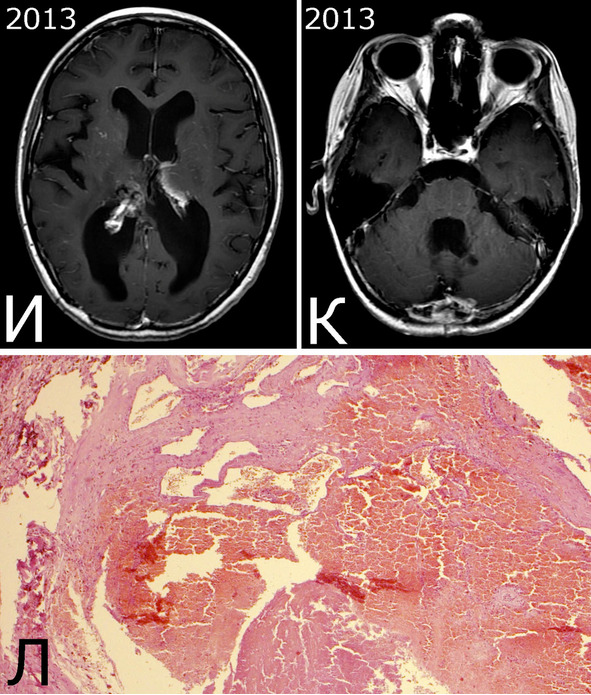

Анамнез (б-ная К-я, 1988 г. р.): в 2001 г (13 лет) обнаружена и удалена (субтотально) глиобластома задних отделов зрительного бугра справа. Проведен курс лучевой терапии. (А – МРТ до операции, режим Т2; Б – МРТ после операции и лучевой терапии, режим Т1). В августе 2002 г произведено радиохирургическое лечение оставшейся части опухоли. При последущих ежегодных обследованиях признаков продолженного роста опухоли не было (В – контрольная МРТ в 2008 г, режим Т1). Неврологического дефицита не было. С января 2011 г после падения на улице появилось пошатывание при ходьбе, которое через несколько месяцев регрессировало. При очередном контрольном обследовании в 2012 г выявлено объемное образование червя мозжечка, расцененное как хроническая гематома (Д, Е – МРТ, режимы Т2, Т1). Кроме того, в режиме SWAN обнаружено множество мелких очагов низкого сигнала, преимущественно перивентрикулярно, имеющих вид КМ IV типа (Ж, З – МРТ, режим SWAN). 01.11.2012 выполнена операция удаления гематомы: Поверхность червя мозжечка в средних его отделах резко изменена, желтого цвета и выбухает. Произведена коагуляция прилежащих участков коры и на глубине нескольких мм обнаружена капсула хронической гематомы. Капсула очень плотная. Она рассечена скальпелем. Содержимое ее – организовавшиеся кровяные сгустки. Помимо основной организовавшейся гематомы было еще несколько крупных полостей с такими же плотными стенками, заполненными кровяными сгустками. С передней части к упомянутому выше новообразованию подходили ветви мозжечковых артерий, которые коагулированы и пересечены. Основные стволы были смещены в сторону и сохранены. Постепенно путем кускования и иссечения фрагментов гематомы, по всей вероятности, и кавернозной мальформации, это новообразование удалено полностью. Оно было окружено измененной мозговой тканью желтого цвета. Ложе удаленной гематомы выложено гемостатической ватой. Образовалась больших размеров полость в пределах верхних и средних отделов червя и прилежащих отделов мозжечка. Гистологический диагноз: ткань мозжечка с капсулой гематомы с кровоизлияниями различной давности, скоплениями макрофагов и сидерофагов, очаговыми лимфоидными инфильтратами. В капсуле гематомы обнаружен микроскопический фрагмент кавернозной мальформации (Л – гистологический препарат, ув. Х 50). МРТ после операции – полное удаление гематомы (И, К – МРТ, режим Т1).